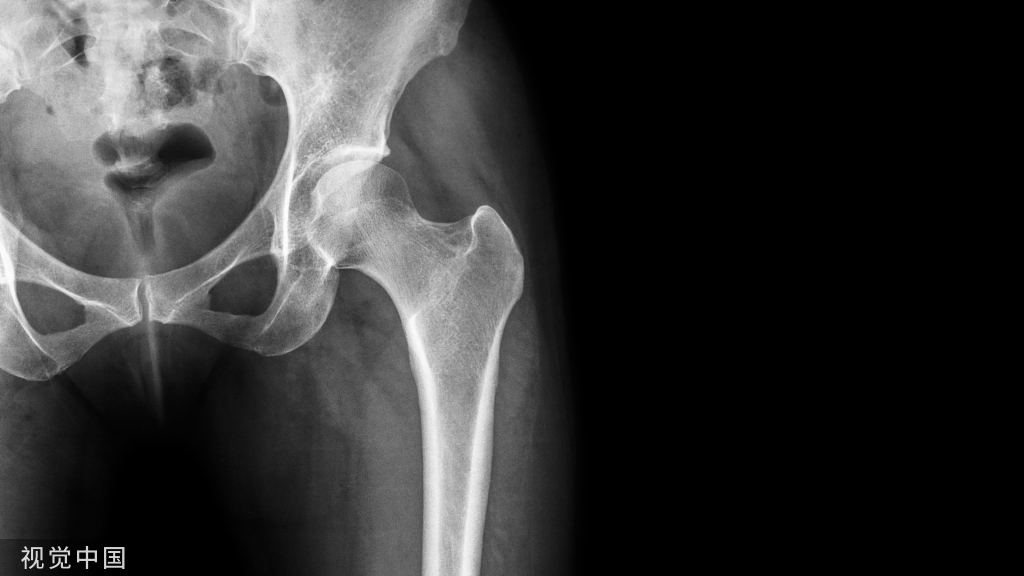

17、 髋臼上缘的副骨:少见。